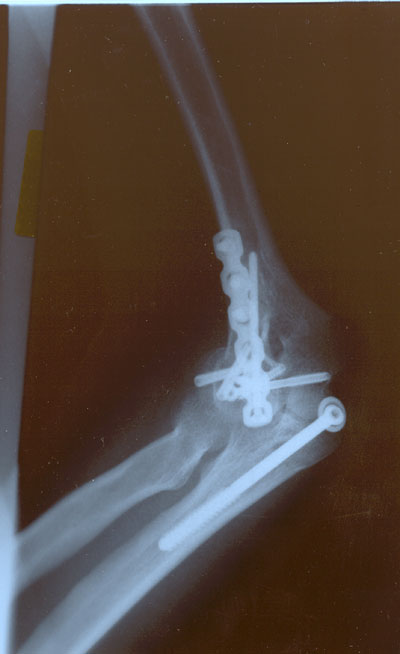

check out my new hardware.